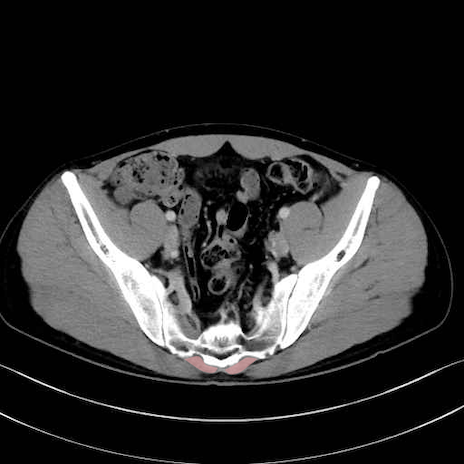

肛門挙筋 (Levator ani)